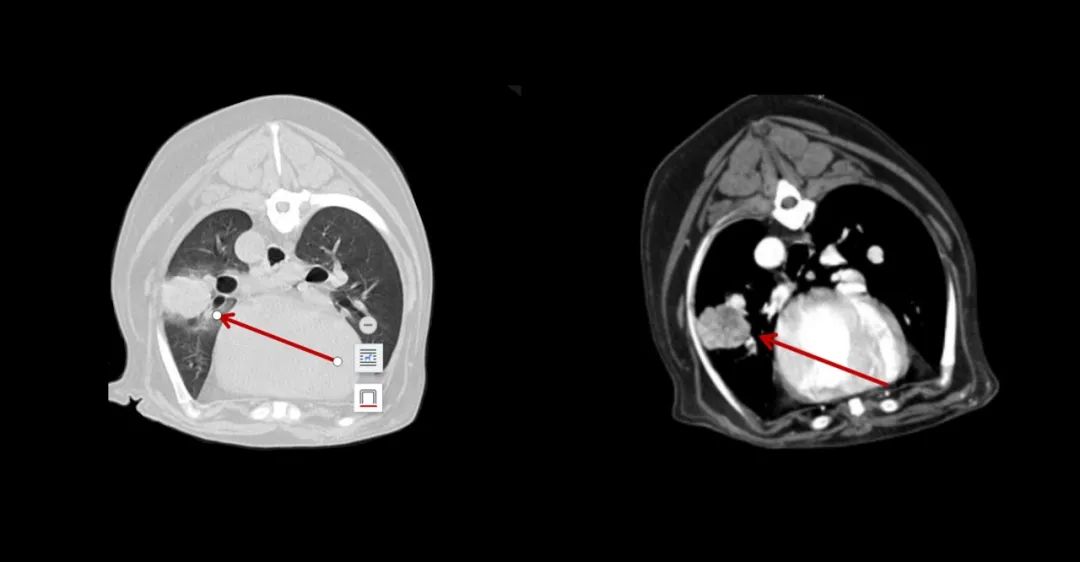

▲7歲成年犬,乳腺癌術(shù)后1年,發(fā)現(xiàn)肺部轉(zhuǎn)移。